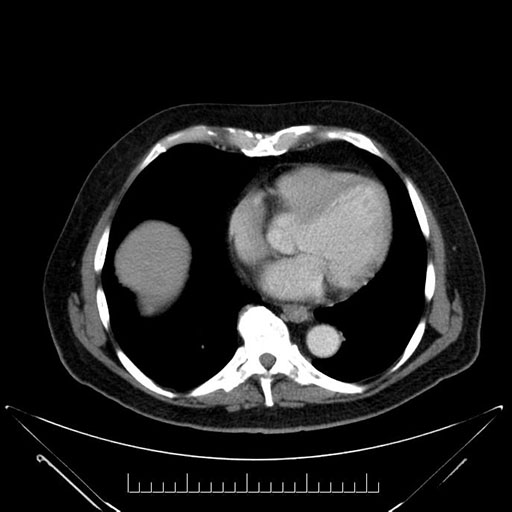

Whipple (pancreaticoduodenectomy) [case 7]

Look through the patient's CT scan to identify any areas of concern for the necessary procedure.

Imaging analysis

Based on your CT findings, which issue(s) would give reason for "planned slowing down moment(s)" in this case?

Considering a standard Whipple procedure, what step(s) of the operation would you do differently in this case?